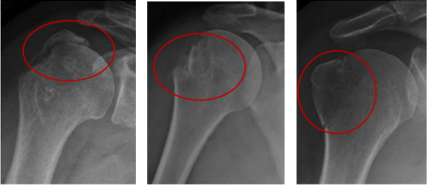

骨折分型:Neer分型

关键数据:5毫米是决定手术与否的“黄金分割线”。研究表明,移位超过5毫米,保守治疗后出现骨不连、畸形愈合和肩关节功能受限的风险显著增加。